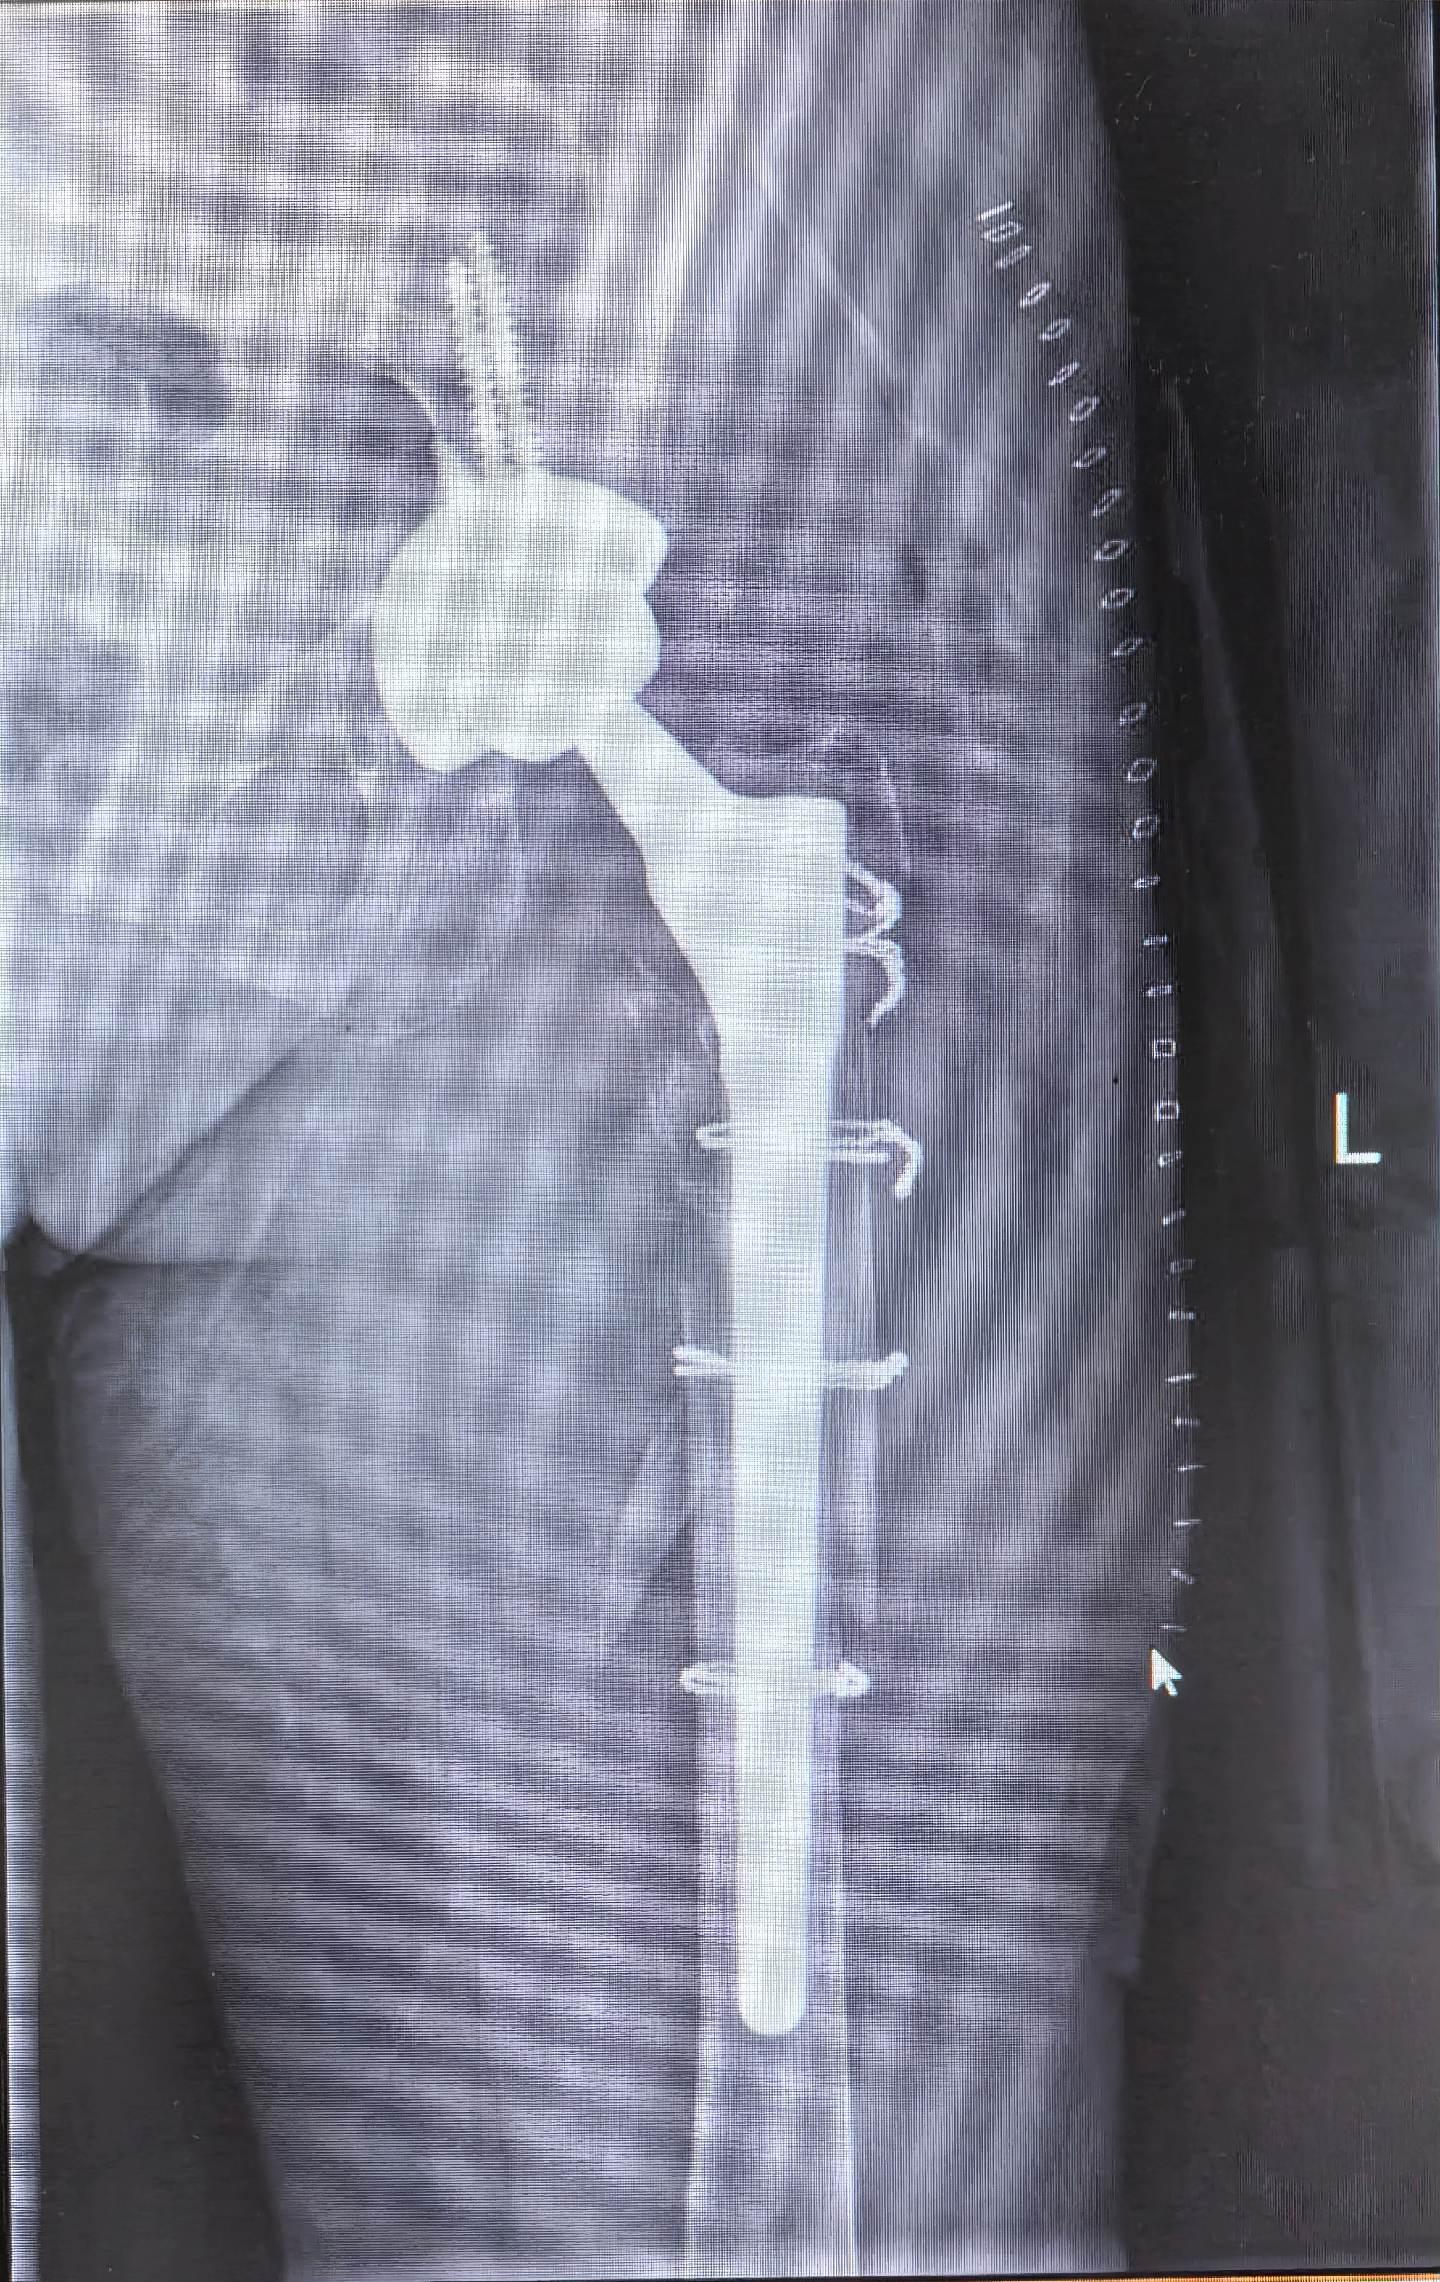

假体周围骨折。髋关节置换术后假体周围骨折,再次翻修,关注老年患者骨质疏松问题,降低骨折发生率。